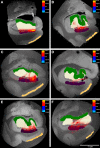

Ex vivo magnetic resonance imaging yields high resolution images that reveal detailed cerebral anatomy and explicit cytoarchitecture in the cerebral cortex, subcortical structures, and white matter in the human brain. Our data illustrate neuroanatomical correlates of limbic circuitry with high resolution images at high field. In this report, we have studied ex vivo medial temporal lobe samples in high resolution structural MRI and high resolution diffusion MRI. Structural and diffusion MRIs were registered to each other and to histological sections stained for myelin for validation of the perforant pathway. We demonstrate probability maps and fiber tracking from diffusion tensor data that allows the direct visualization of the perforant pathway. Although it is not possible to validate the DTI data with invasive measures, results described here provide an additional line of evidence of the perforant pathway trajectory in the human brain and that the perforant pathway may cross the hippocampal sulcus.